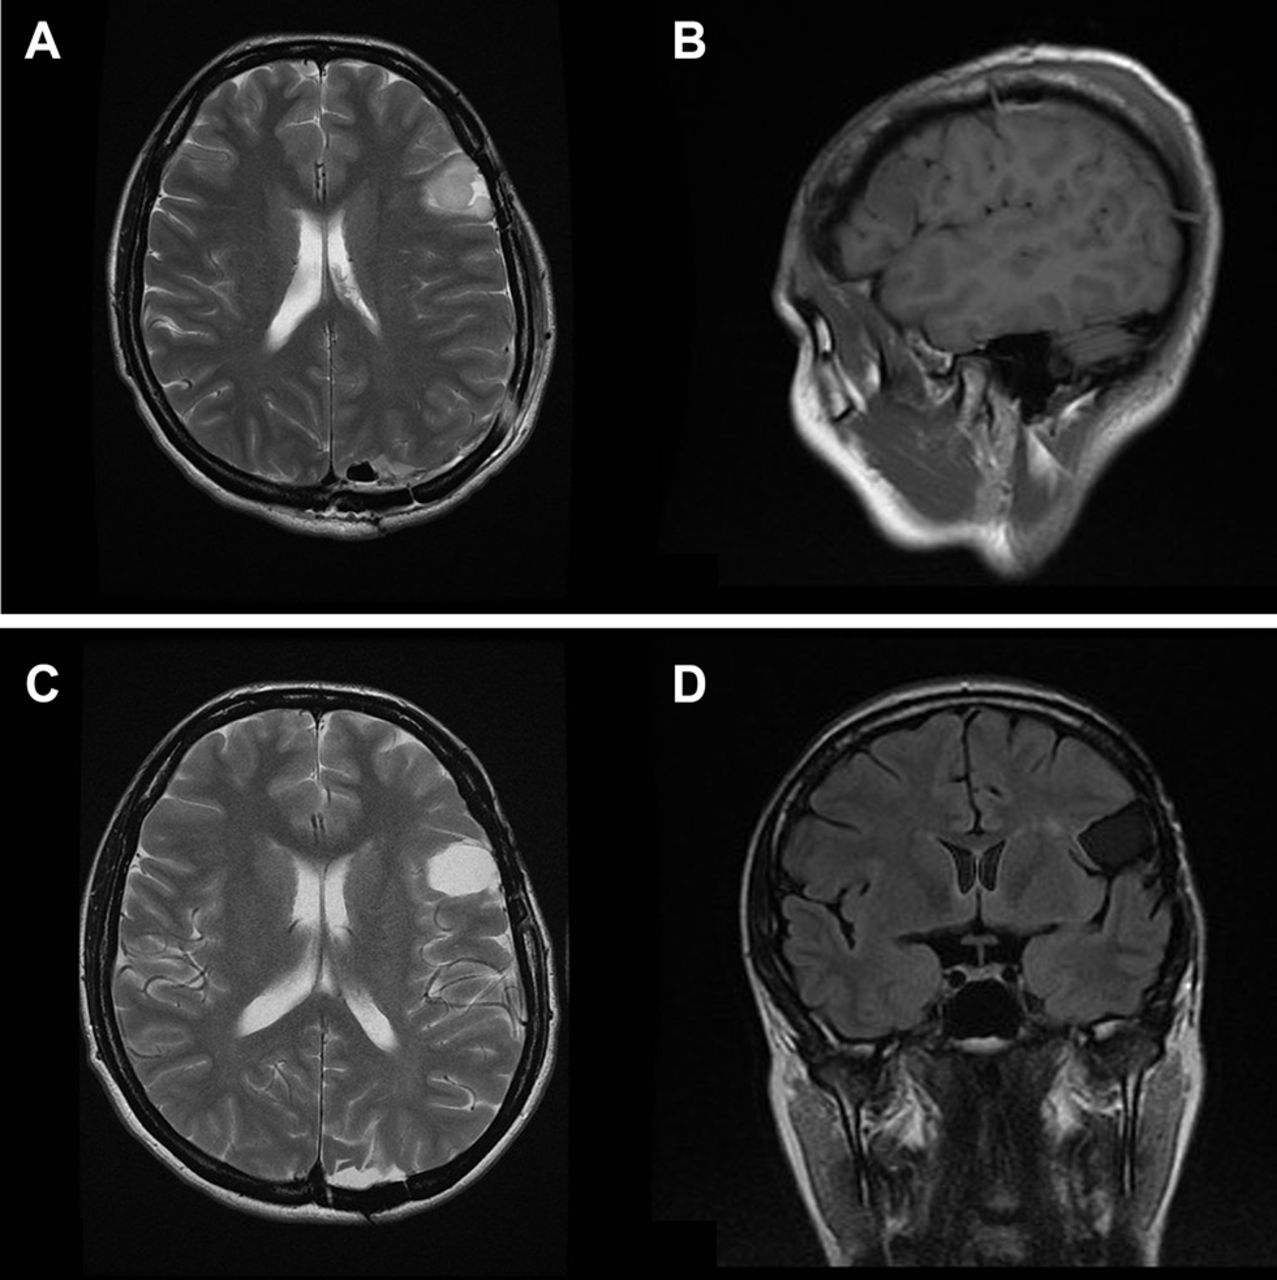

引言:2级胶质瘤(低级别胶质瘤)越来越多地在接受MRI检查的患者中被偶然发现。较近的研究数据表明,这种偶发的低级别胶质瘤是进展性肿瘤,经过临床转...

神经胶质瘤是中枢神经系统常见的原发肿瘤,在美国每年发病率约为每10万人6.6例。约50%的胶质瘤患者表现为WHO IV级(胶质母细胞瘤)。高级别脑胶质瘤患者的...